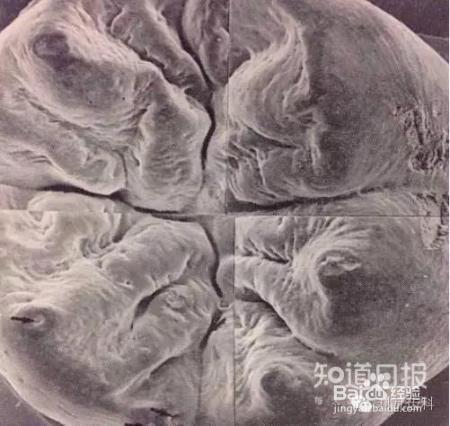

(图为扫描电子显微镜下拍下的磨牙咬合面,这些沟窝,肉眼不容易看出来的。这些缝隙就像我们装修时地砖的缝隙一样,如果认真封好就不会漏水,不会进脏物。)

窝沟就是第一恒磨牙(即后槽牙)咀嚼面上的凹坑和裂隙,细菌和食物容易存积此处。刷牙、漱口等方法很难深入窝沟,只要把窝沟部位保护好,就会大大降低儿童患龋齿的可能性。